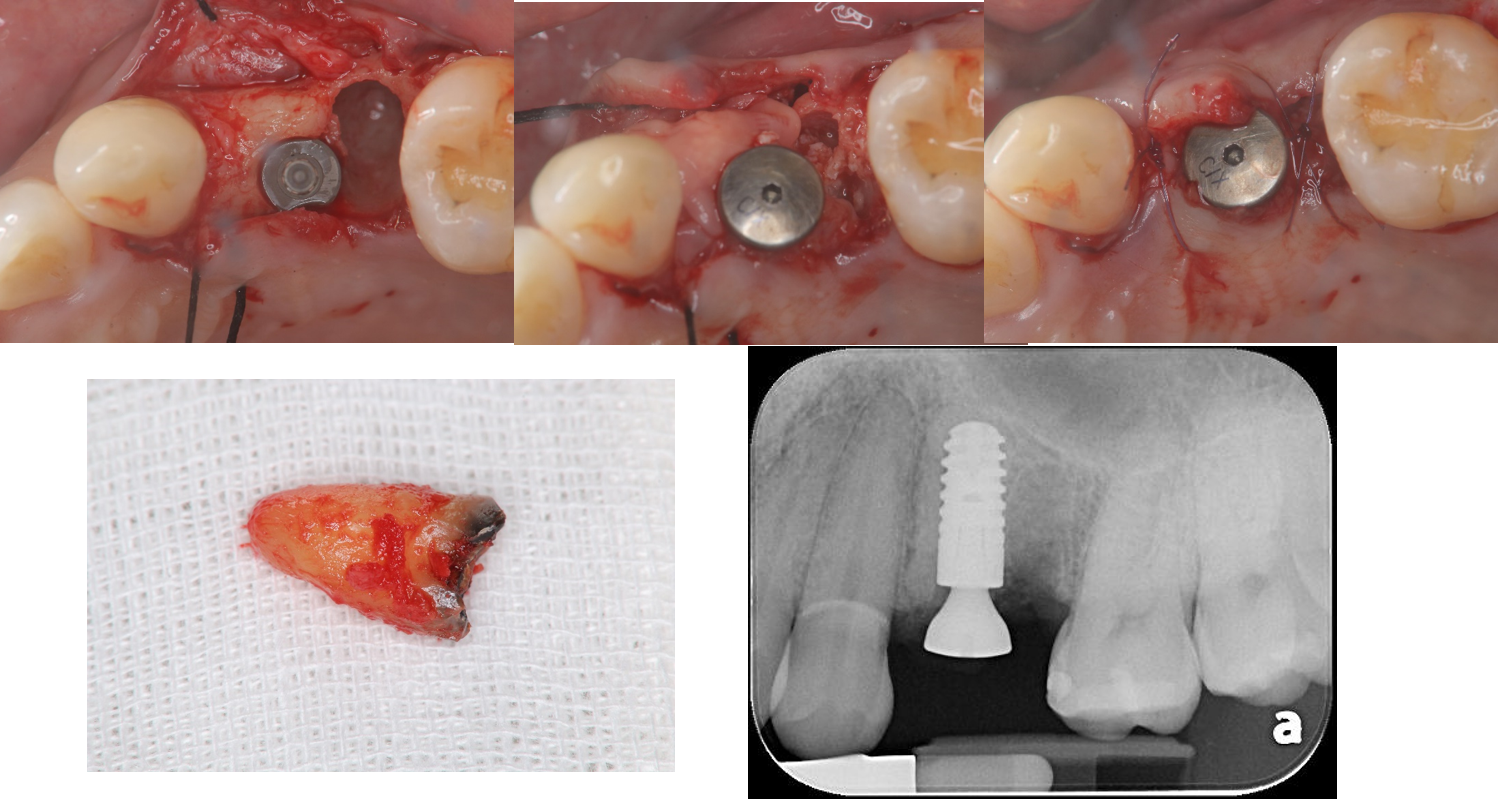

上顎拔牙及植牙補骨

下顎植牙